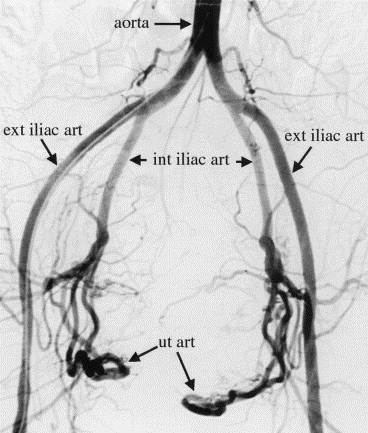

In UAE, imaging is done by a Vascular and Interventional Radiologist. This procedure differs from surgery, where large cuts are made to physically remove tissue. For Uterine Artery Embolization, a small puncture and a thin instrument called a catheter are employed. The procedure aims to regulate blood flow. This is achieved through the uterine arteries, whose function is to deal with the condition causing symptoms. Dr. Rakesh Kumar Kumawat is greatly trusted for his work involving minimally invasive methods since he is a proponent of precision medicine. Indeed, if a woman’s life is impacted due to her period of bleeding and pain and/or pressure symptom due to a possible ovarian cyst, not only should she find relief, but it should happen in a manner that is convenient to her.

In the UAE treatment, imaging guidance is utilized to ensure the catheter passes safely through blood vessels to reach the precise area of the uterine arteries. Smaller particles are finally infused to lower blood supply for the specified areas of the uterus. Over the period, the body compensates for the foreign matter by shrinking the sizes of the fibroids or adjusting the bleeding patterns.

Step 3: Access and Catheter Navigation A small puncture is made, most commonly in the groin, but sometimes the wrist is preferred depending on technique and preference. A smaller catheter is then introduced into the artery under imaging guidance to go to the uterine arteries.

It requires choosing the proper expertise, planning, and follow-up care to get the best Uterine Artery Embolization Doctor in Jaipur, not just a clinic. The UAE is a minimally invasive intervention treatment that requires precision imaging guidance, skilled catheter navigation, and an excellent knowledge base regarding pelvic vascular anatomy.